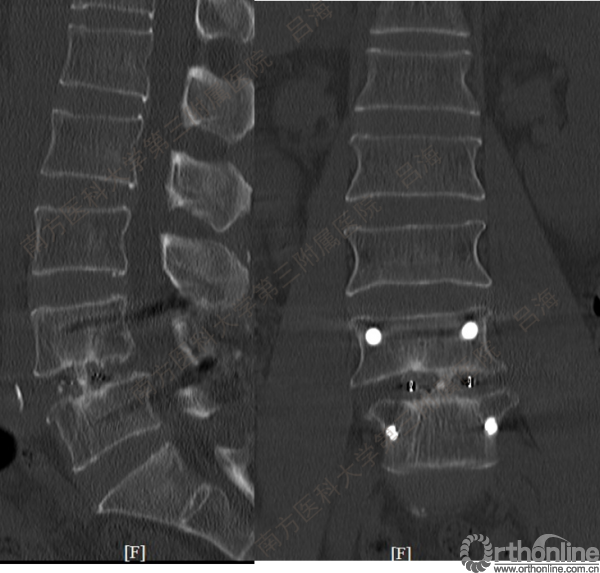

随着社会老龄化进程加快,胸腰椎退行性病变的治疗已经成为脊柱学术界的一个热点话题。MIS-TLIF手术可以治疗多种不同的胸腰椎退行性疾病,南方医科大学第三附属医院吕海教授结合病例为我们一一展示了该术式在治疗不同胸腰椎疾病时的具体手术过程。